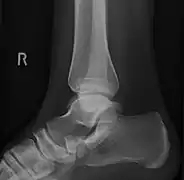

Radiological images

From left to right: Type 1, 2 and 3